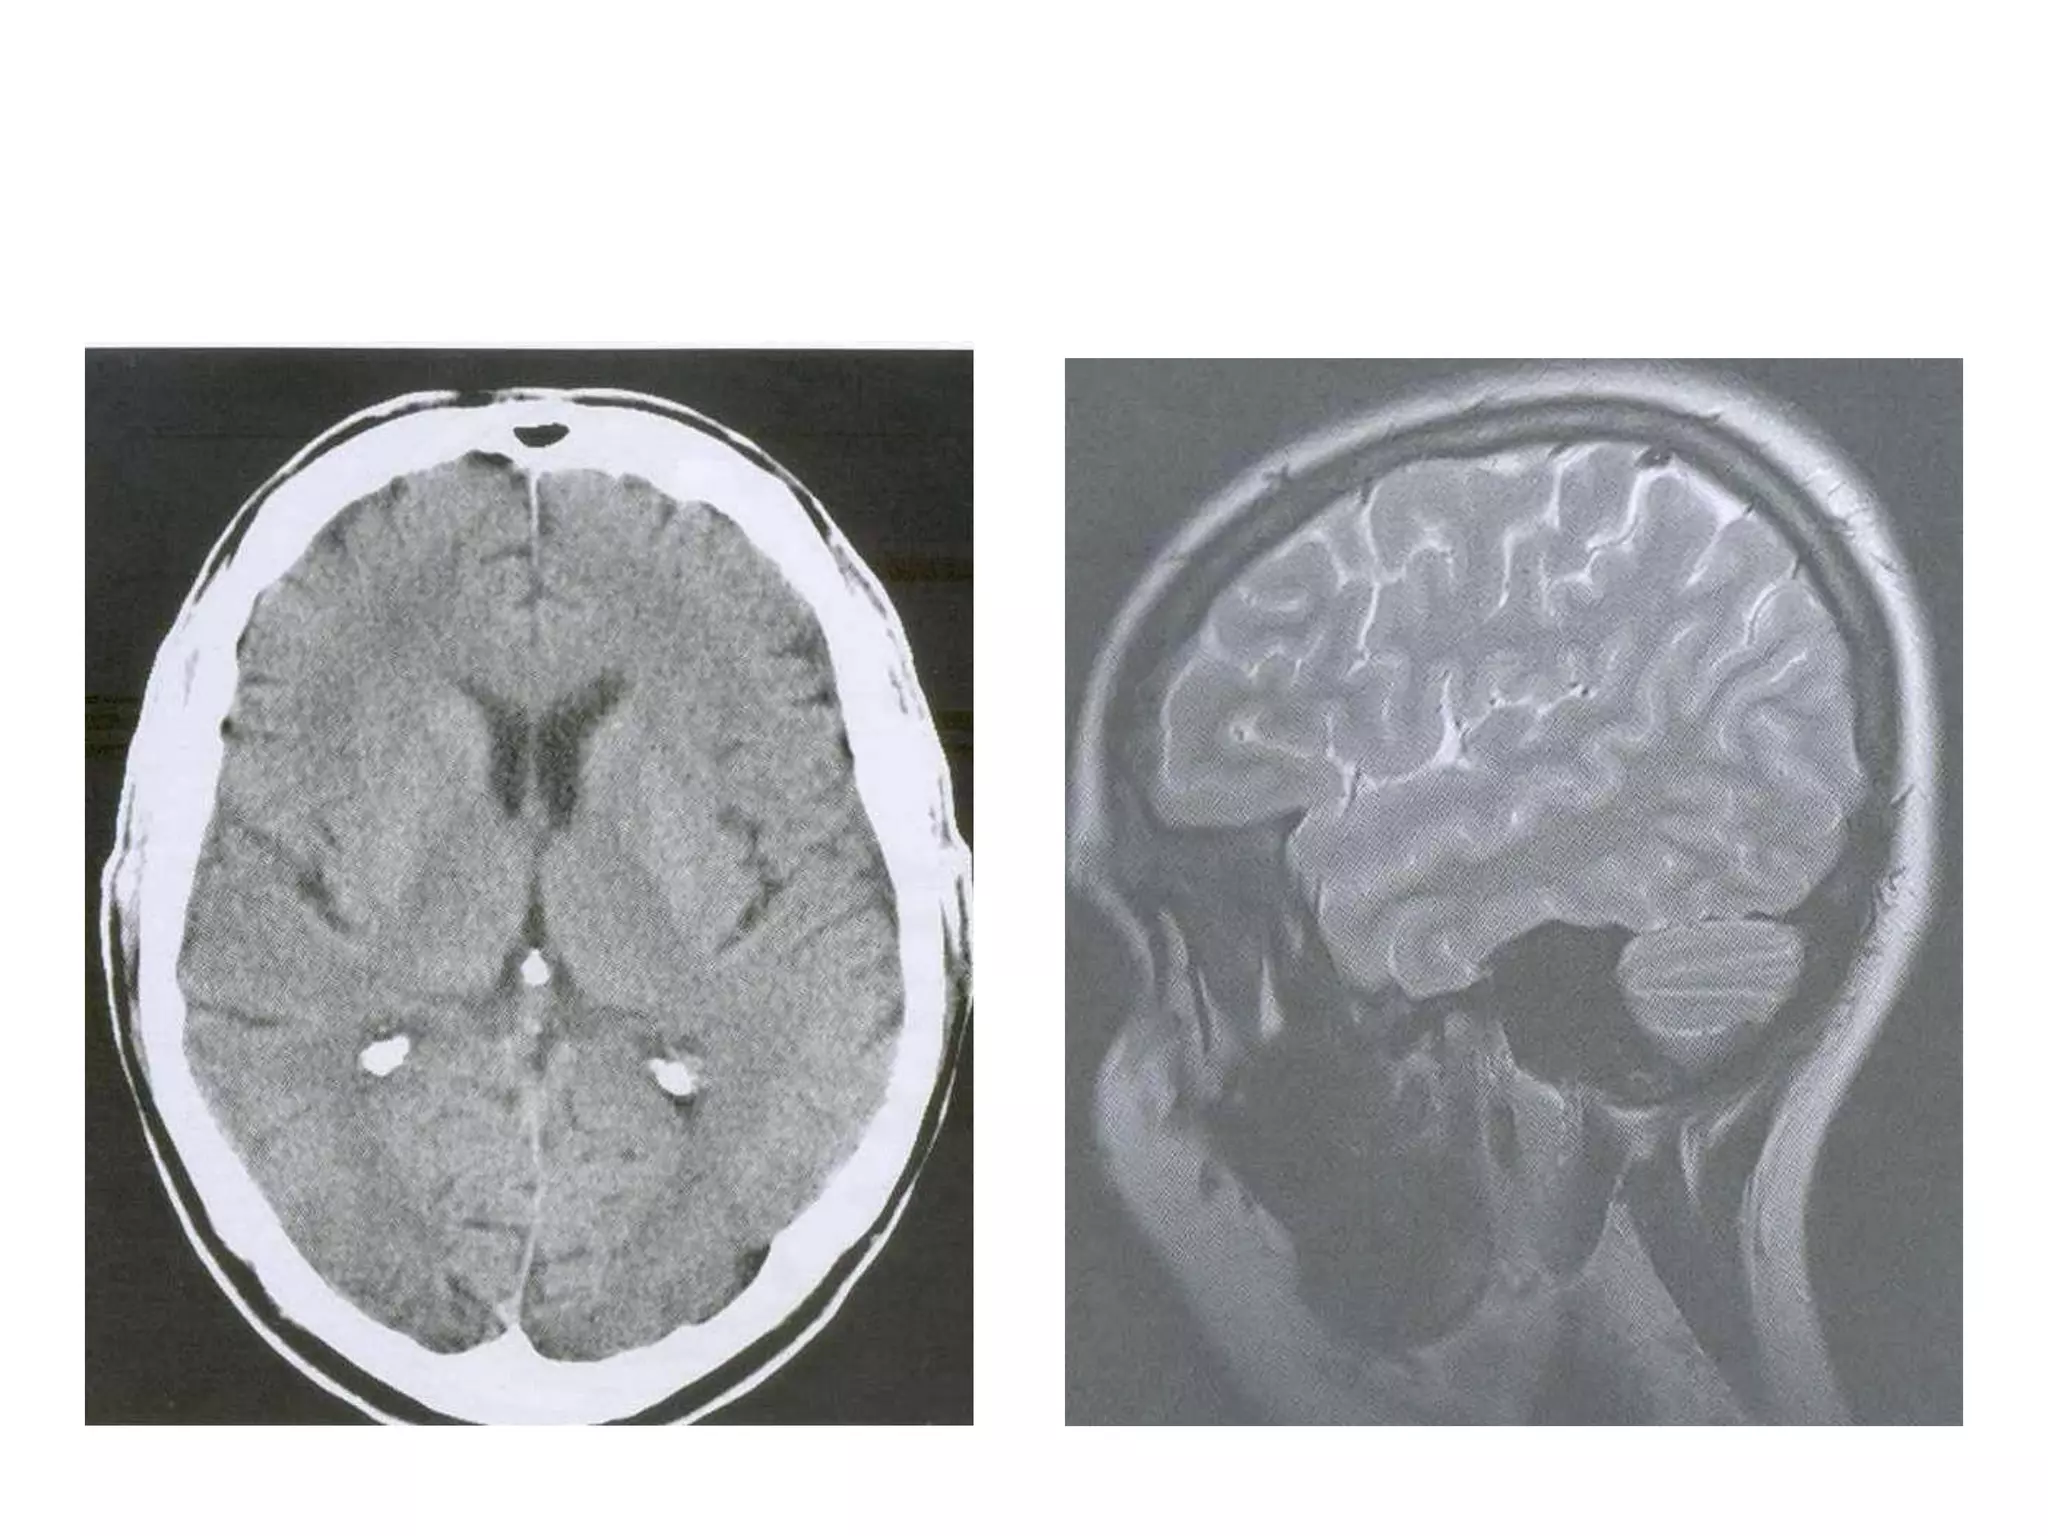

Radiology

• Axial MRI / CT – ‘kidney bean’ turned on its side.

• Saggital MRI - mid point of line drawn b/w T. sella

and trocula should intersect middle of 4th

ventricle.

• Coronal MRI – elongated rhomboid shape

• Radiology –

Axial MRI / CT - narrow cleft

Saggital MRI – elongated and complex curved shape

with upward, backward & downward arc.